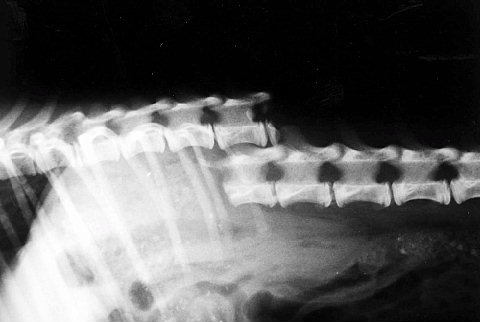

次の症例は子犬なんですが、放し飼いをしていて他の犬に噛まれたという事例です。

背骨が完全に折れてます。これは脊髄も断裂していますから骨の手術をしても下半身麻痺となります。